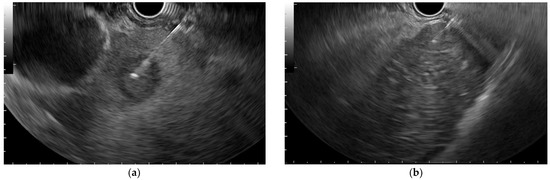

3.2. B-Mode EUS Assessment